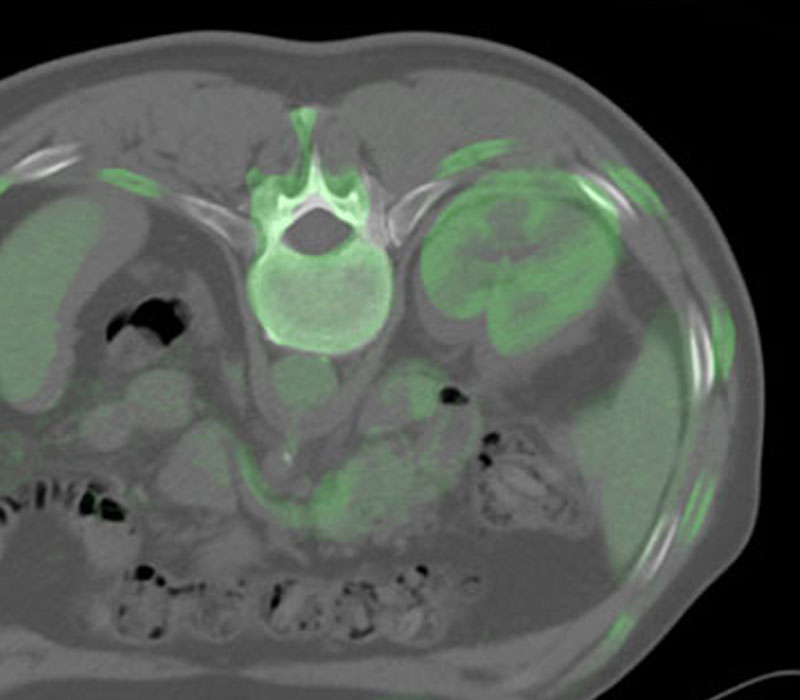

IGTFusion used to guide and confirm accurate needle placement in 3 renal lesions that were not visible on CT during the procedure.

- Registered a supine pre-procedural image to a prone procedural image